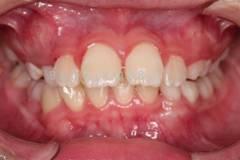

下面這個小患者就存在需早期矯正的問題。通過早期矯正,在不長的時間內(nèi)就達(dá)到極為明顯的療效。她的情況如果等到牙齒替換完畢后再解決,矯治的難度則會非常大。

早期矯正中